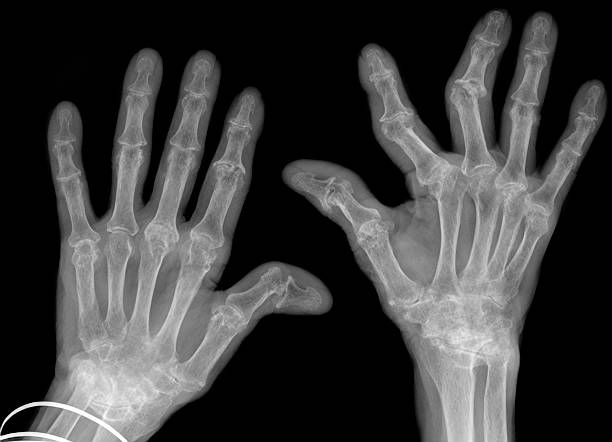

류마티스 관절염은 활막이 존재하는 모든 관절에서 발생하는데 활막은 관절 주위를 둘러싸고 있는 조직으로 자가면역 기제에 이상이 생기면서 나타나는데 자가면역 이상은 외부 공격으로부터 신체를 보호하는 대신 공격하는 면역 체계의 이상으로 다양한 연령대에서 나타나고 있으며 우리나라 인구 1% 정도가 겪고 있는 것으로 알려져 있어 다른 질환과 마찬가지로 초기에 증상을 파악하고 대응하는 것이 좋습니다.

류마티스 관절염 초기증상 열 번째는 뻣뻣한 손과 발입니다. 류마티스 관절염의 초기 단계에서는 후관절에서 증상이 나타난다. 해당 증상은 손가락과 손이 만나는 관절이나 발가락과 발 사이의 관절에서 시작되며 시간이 지남에 따라 이 뻣뻣함이 다른 관절로 옮겨갈 수 있습니다. 증상은 아침이 아닌 하루 중 언제든지 나타날 수 있습니다.